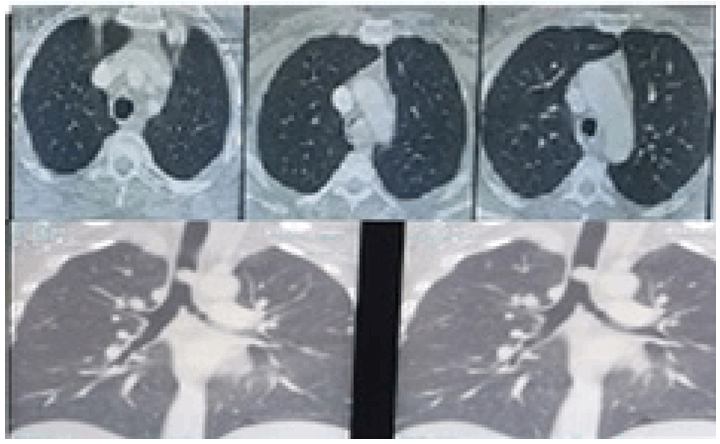

A 45-year-old female, nonsmoker, presented to casualty with tachypnea and tachycardia. She was admitted to the intensive care unit with respiratory acidosis. There was a history of irritant cough with expectoration and breathlessness since 20–25 days. A past history of hyperthyroidism was noted, for which she was on treatment since last six months. After admission, she was diagnosed with diabetes mellitus incidentally. Chest X-ray showed mediastinal widening. Computed tomography (CT) scan suggestive of 2x1.8 cm sized enhancing polypoid lesion arising from the lateral wall of the distal trachea, just proximal to carina, protruding into the lumen, almost obliterating the entire tracheal lumen (Figure 1).

On postoperative day (POD) 1 the patient developed respiratory distress with air bubbling in the mediastinal drain. Check bronchoscopy showed a gape in suture line in posterior wall of trachea along the left lateral aspect over a region of 1–2 stitches. After a multidisciplinary meeting (MDM), it was decided to reintubate the patient to reduce airway pressures and the patient was kept on a T-piece with spontaneous breathing. The bubbling in the drain stopped post-intubation. On POD 3 after a repeat MDM patient extubated. On POD 5 the patient shifted out of ICU with full Ryle's Tube feeds. On POD 7 check bronchoscopy done suggestive of granulation tissue noted over the gaped area. Rest of the suture line was normal. With symptomatic improvement and serial chest X-rays suggestive of reduction in mediastinal widening patient discharged on POD 14. Final histopathology report confirmed adenoid cystic carcinoma of the trachea with negative margins with no lymphovascular emboli or perineural invasion and negative lymph node (Figure 4A-B). Postoperative adjuvant radiotherapy of 56 Gy in 28 fractions for 46 days given to the tumor bed with three-dimensional conformal radiation therapy. She is on six monthly follow-ups with check bronchoscopy and annual CT scan. The patient remains asymptomatic with normal check bronchoscopy (Figure 5) and CT scan at 18th month post-procedure.

Figure 1: Computed tomography scan showing polypoid lesion arising from the lateral wall of the trachea just proximal to carina protruding into the lumen and almost completely obliterating lumen.

Figure 5: Post-procedure after bronchoscopy showing scar mark of previous surgery.